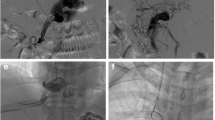

During a median follow-up of 14 months (range 5–39 months), four patients developed overt HE (West Haven Grading System). They received treatment with medications, such as L-ornithine L-aspartate, lactulose, and rifaximin. Symptoms resolved in one patient after 3 months of TEPS. However, the other three patients continued to experience intermittent grade 2–3 HE. These three patients also developed chronic liver failure. Despite etiological treatment, efforts to eliminate jaundice, promote hepatocyte regeneration, and provide albumin or plasma support, along with necessary artificial liver treatment, were unsuccessful, and these patients succumbed within 7–16 months. Another patient died due to the progression of hepatocellular carcinoma. Shunt dysfunction did not occur in any of the patients during the follow-up. The details of the procedure and outcomes are provided in Table 3, and clinical and biochemical follow-up results are detailed in Fig. 3.

Changes in total bilirubin (TBIL), ammonia, hemoglobin (Hb), international normalized ratio (INR), Child–Pugh (CP) score, and Model for End-Stage Liver Disease (MELD) score were evaluated at various time points. The assessments included measurements before TEPS (n = 22), 3–7 days post-TEPS (n = 22), and 4–6 weeks post-TEPS (n = 22). Furthermore, a subgroup of patients received follow-up at 12 months post-TEPS (n = 9)